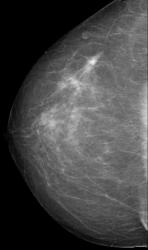

СЛУЧАЙ РЫБАКОВОЙ Л. А. "Инфильтрирующий рак правой молочной железы".

"Инфильтрирующий рак правой молочной железы".

Каюсь, вина моя. Людмила Александровна указала, что имеется "мультифокальный рост".

Если честно, по поводу жалоб даже не помню, надо амб. карту поднять.Часто бывает,что такие больные ни на что не жалуются, либо незначительная болезненность.В таких случаях не бывает симптома площадки или "лимонной корки",кожа никак не меняется.